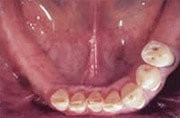

Fehlen mehrere Zähne, so spricht man vom teilbezahnten Kiefer. Solche größeren Zahnlücken konnten früher oftmals nur mit herausnehmbaren Teilprothesen geschlossen werden, wenn eine Brückenversorgung nicht mehr möglich war. Implantate erlauben, die Lücke mit einer implantatgetragenen festsitzenden Brücke zu schließen, ohne herausnehmbare Prothesen und ohne Abschleifen gesunder Nachbarzähne.

Ersatz der Unterkiefer-Seitenzähne beidseits mit natürlich aussehenden, festsitzenden Brücken und Kronen auf Implantaten.